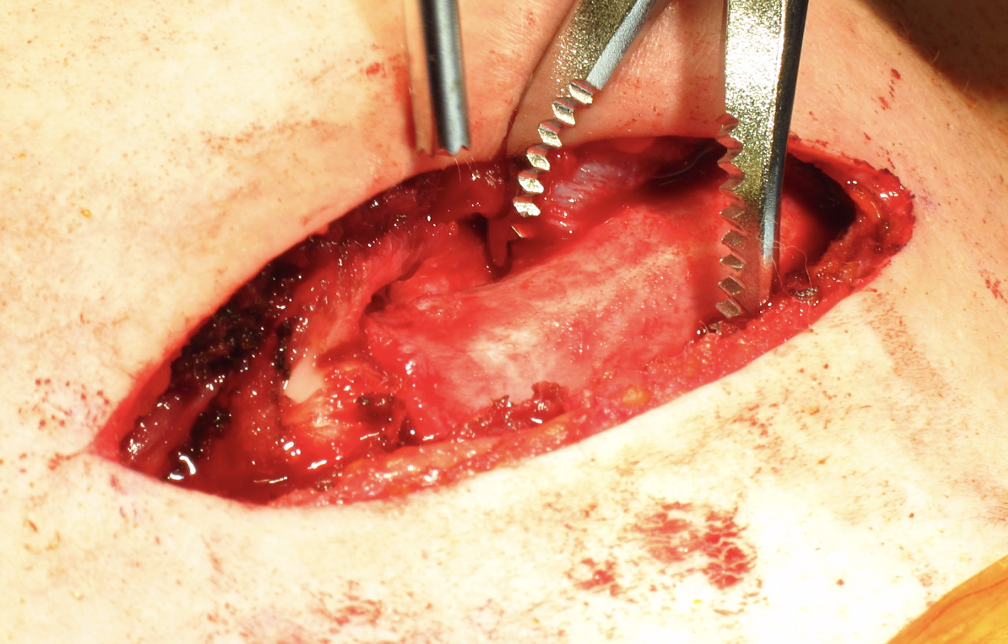

2. Open reduction

Performed under GA in operating room

- chest surgeon available

- potential vascular / airway catastrophe associated with injuries to the mediastinum

Technique

Open reduction of acute posterior sternoclavicular joint dislocation

Drill holes in manubrium and medial clavicle

Figure of 8 suture fixation